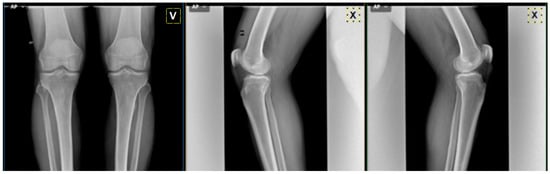

| Knee image | ![]() | ![]() | ![]() | ![]() | ![]() | ![]() | ![]() |

| MedKnee | KL-0 | KL-3 | KL-3 | KL-2 | KL-3 | KL-4 | KL-0 |

| Rheumatologist | KL-1 | KL-2/KL-3 | KL-4 | KL-1 | KL-4 | KL-3 | KL-1 |

| Radiologist | KL-0 | KL-1 | KL-3 | KL-2 | KL-3 | KL-2 | KL-1 |